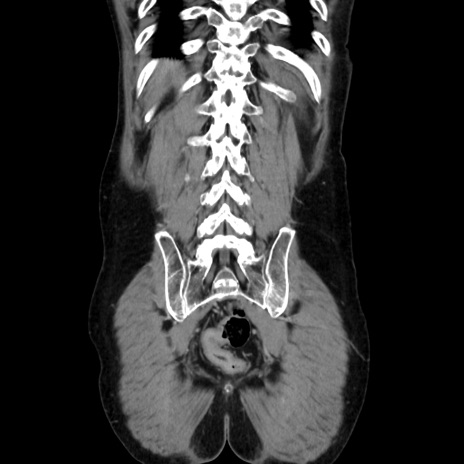

症例37(冠状断像)

【症例】40歳代 男性

【主訴】腹痛

【現病歴】4時間ほど前に電車に乗車中に臍部上より腹痛出現。徐々に増悪し起立困難となり、救急外来受診。生ものは数日食べていない。今朝お雑煮を食べた。

【身体所見】BT 36.8℃、BP 117/84mmHg、HR 91/min、SpO2 97%、苦悶様、腹部:臍上部広範囲圧痛あり、反跳痛±

【データ】WBC 8100、CRP 0.03